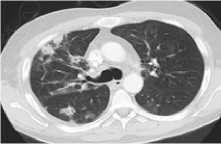

Примеры наиболее частых пульмонитов представлены на рисунке 1.

Пульмонит с картиной мозаичной плотности, изменения по типу гиперчувствительности (ГП)

Рисунок 1. Виды Л-ИЗЛ